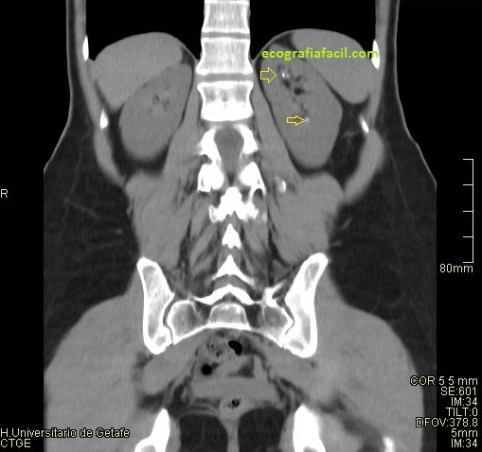

Al realizar la ecografía consigo demostrar una litiasis muy ecogénica con una potente sombra acústica posterior en el polo inferior del riñón derecho. En la petición del especialista se especificaba control de litiasis bilateral, sin embargo, en el otro riñón no había ni resto de litiasis. Pregunté a la paciente si había tenido cólicos nefríticos expulsivos (con expulsión de piedra) desde el último control, su respuesta fue negativa. Dado que tenía controles previos, los consulté, en la última eco realizada, 8 meses atrás no había piedras en el riñón izquierdo, donde yo no había visto en la actualidad, pero ví que entre una y otra ecografía había un TC de Abdomen sin contraste. En el TC se observaban litiasis renales milimétricas, varias, en el seno renal izquierdo, invisibles en la ecografía.

La secuencia de imágenes que has visto es el proceso que ha llevado la paciente, con una ecografía antes del TC con el mismo resultado en cuanto a litiasis que la última que corresponde con las imágenes 6, 7 y 8 donde puedes ver la litiasis renal derecha grande, en el grupo calicial inferior en longitudinal y en transverso. Riñón izquierdo rigurosamente normal, por más que pude buscar, aún a sabiendas de que en el TC habían salido piedras en ese riñón, además, agrupadas en los diferentes grupos caliciales, imágenes 2 y 5, en las reconstrucciones coronales como en los cortes axiales, pero llama poderosamente la atención como junto a la litiasis del RD en el TC, imagen 3, se ven otras dos pequeñas litiasis, imagen 4, que tampoco pude objetivar en la ecografía, ni se vieron en la ecografía anterior. La Rx señala la vista en las ecografías.